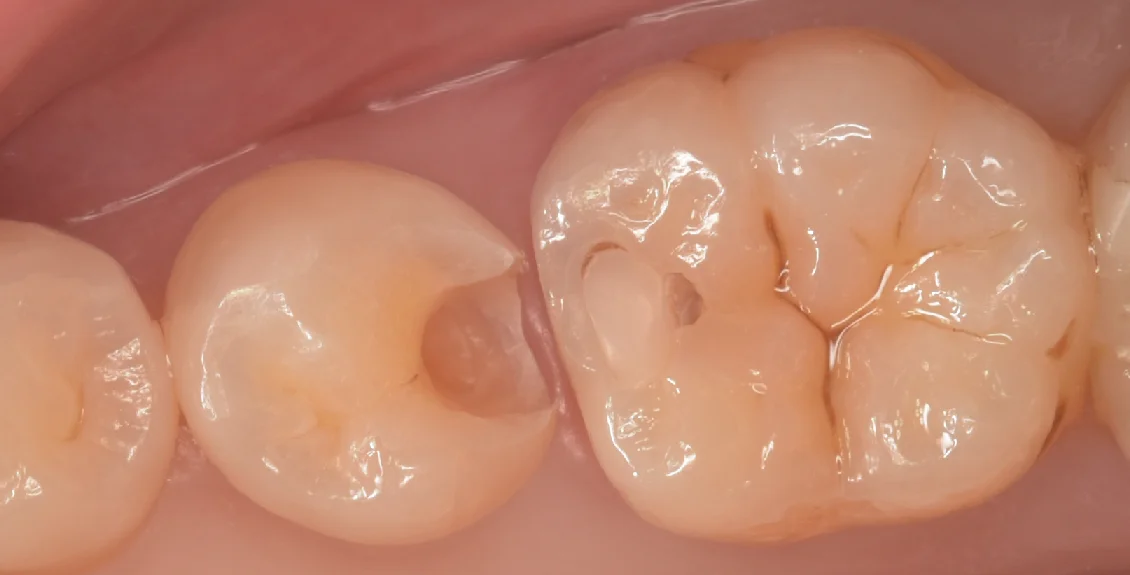

そして虫歯を取り切ったのがこちらになります。

本来の歯の色が綺麗にでたのがわかるかと思います。